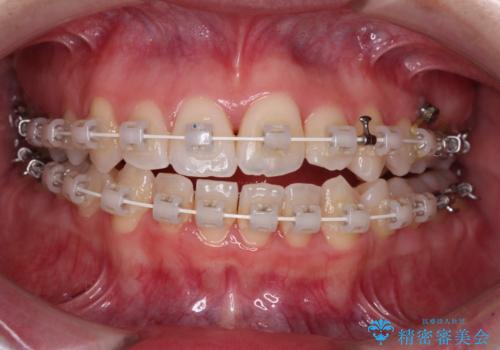

- 矯正装置

- 審美装置

- 治療期間

- 3年8ヶ月

事前に急速拡大装置で側方拡大を行い、上下を目立たないワイヤー装置により歯列を整えていくこととしました。

急速拡大装置により骨格はある程度改善されましたが、奥歯の咬み合わせ改善に非常に時間がかかってしまいました。

デコボコを改善させるだけでなく、しっかりとした咬合状態を獲得することができ、患者様には大変満足していただけました。